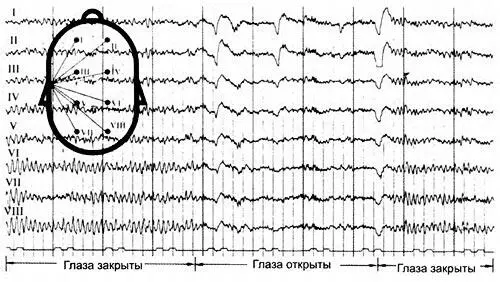

У человека также есть множество биологических часов, ритмы которых регулируют метаболизм, активность и т. д. Нашим главным регулятором является мозг с его различными внутренними ритмами. Минимальная длительность событий в коре головного мозга составляет 70 миллисекунд. Наше зрение воспринимает последовательный процесс сериями из 16–18 образов в секунду; наш слух воспринимает звуки с частотой в 18 колебаний в секунду. Все они образуют мгновенные «ощущения» человека. (Альфа, бета и другие ритмы изображены на приведенной слева электроэнцефалограмме. Фрейзер и Лоуренс, том II, стр. 65).